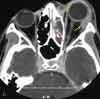

In this patient, a laryngeal injury is suspected.You order a CT scan of the neck to further investigatethis possibility. An axial image filmed in bone windowsat the level of the thyroid (B) and an axial image filmedin soft tissue windows at the level of the mandible (C)confirm the finding of retropharyngeal gas (arrows).However, no clearly defined track of gas extends fromthe esophagus or trachea. There is also no clear evidenceof hematoma.

You order a Gastrografin swallow. This anteroposteriorprojection of an esophagram at the level of the softtissues of the neck reveals a clear leakage of contrastmaterial from the cervical esophagus at approximatelythe level of the C6 vertebral body (D, arrow).